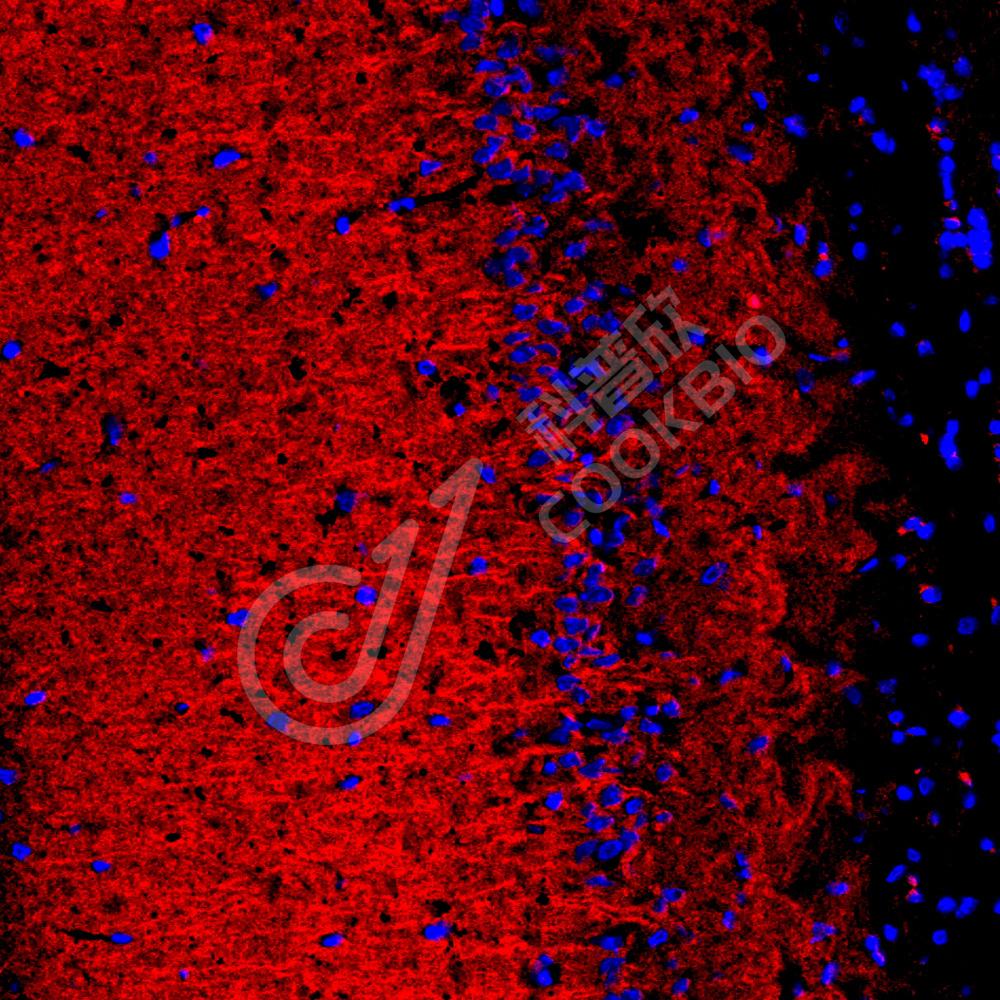

IF检测Tau蛋白(货号 K1334827)(红色).

样品: 大鼠脑, 4%多聚甲醛 (货号KSG1101) 固定12-24小时.

抗原修复: Tris-EDTA抗原修复液(pH 9.0) (KSG1203), 98℃, 20分钟.

封闭: 3% BSA(货号KSGC305010)的PBS溶液, 室温孵育30分钟.

—抗: 1: 1500稀释, 4℃ 孵育过夜.

二抗: Cy3标记山羊抗兔IgG (H+L) (货号KB63909), 1: 300稀释, 室温孵育1小时.